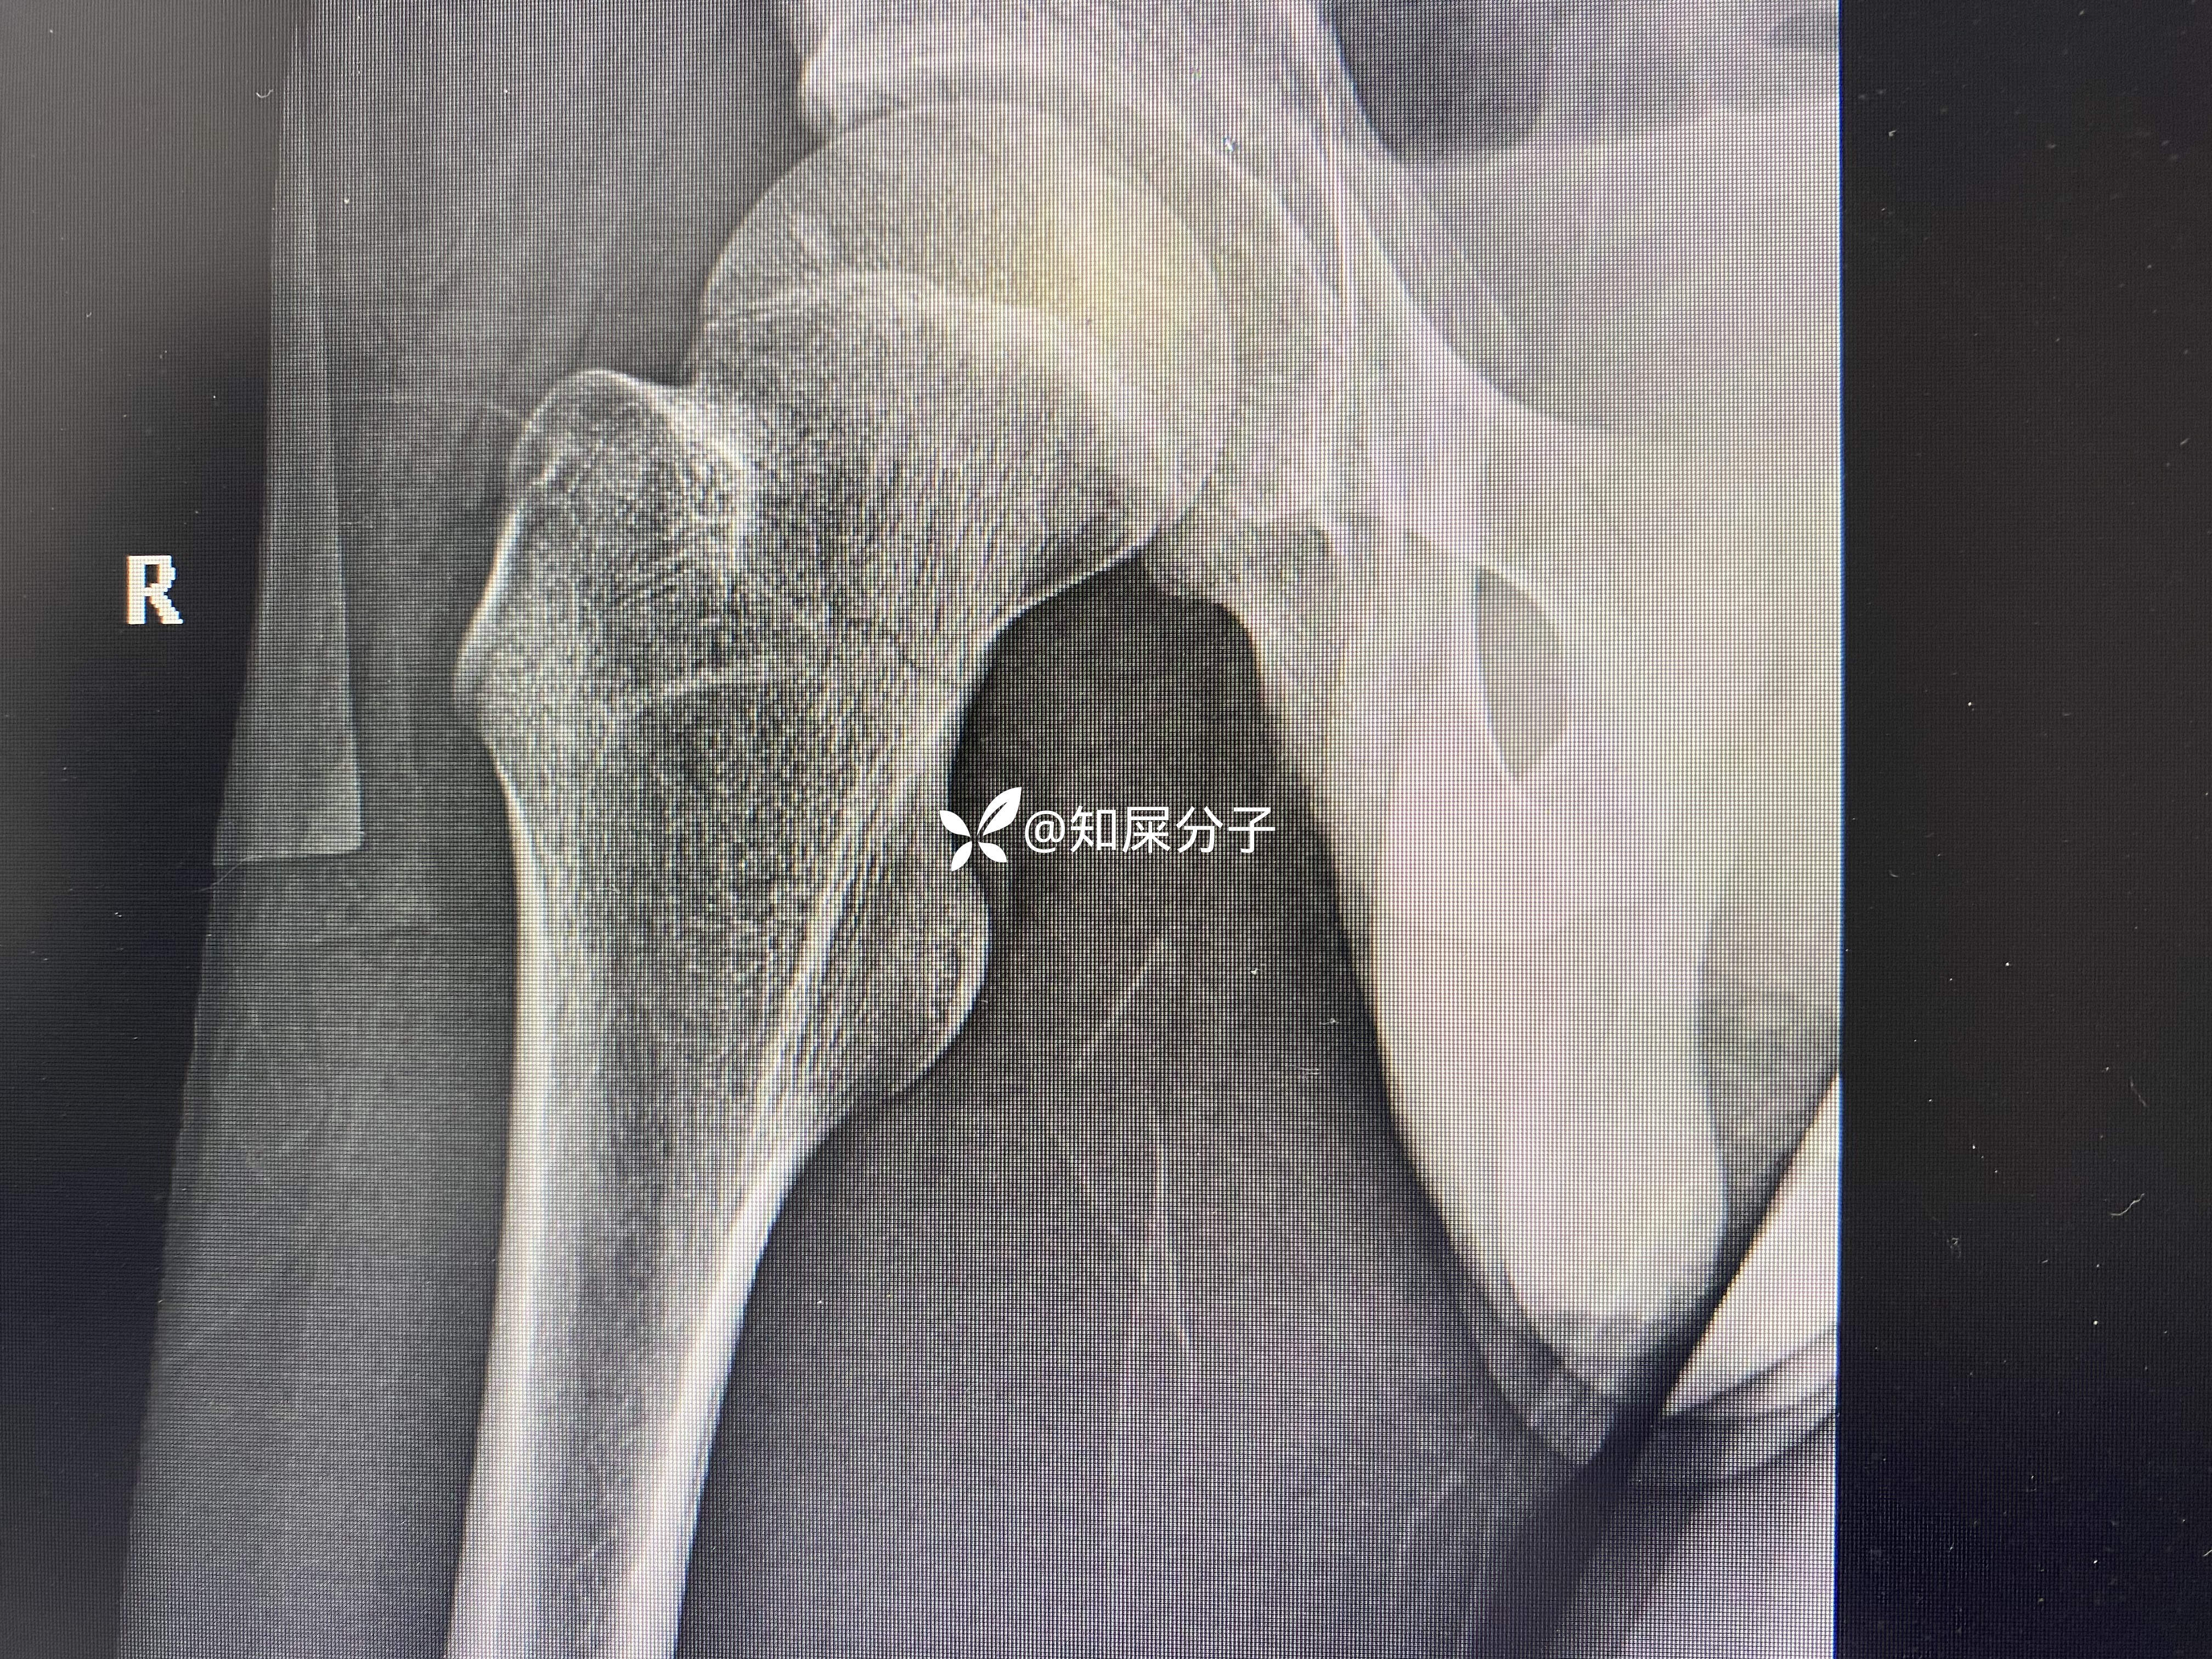

男,17岁

入院检查如下: